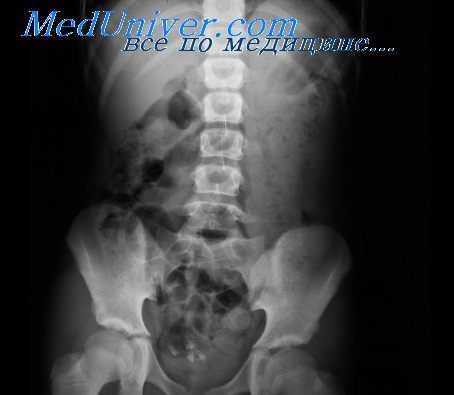

Рубцовые (спаечные) процессы. При рубцовых изменениях стенки кишки и перивисцерите, обусловленных чаще всего воспалительно-деструктивными процессами, возникают деформации и разной степени сужения (стенозы) просвета кишки в зоне поражения. Деформация и стеноз кишки могут быть связаны также с оперативным вмешательством.

При рубцовом изменении стенки кишки выявляется сужение ее просвета, обычно циркулярное, несколько асимметричное. Контуры измененного участка неровные, волнистые, извитые. Эластичность и сократительная способность стенок кишки нарушены незначительно, а в области перехода суженного участка в неизмененный или несколько расширенный отсутствует подрытость контуров, свойственная раковой инфильтрации. Степень супрастенотического расширения кишки определяется величиной и локализацией стеноза, наличием сопутствующего воспалительного процесса и спазма, а также давностью заболевания. При этом стенки расширенного участка сохраняют нормальную эластичность, рельеф же слизистой оболочки из-за сопутствующего стенозу воспаления обычно перестроен.

Рубцовые сужения кишки дифференцируют с функциональными сужениями (спазмами) и опухолевыми стенозами, а возникшие при перивисцеритах тракционные (вторичные, приобретенные) дивертикулы, имеющие широкое основание и конусовидную форму, — с активным язвенным процессом.